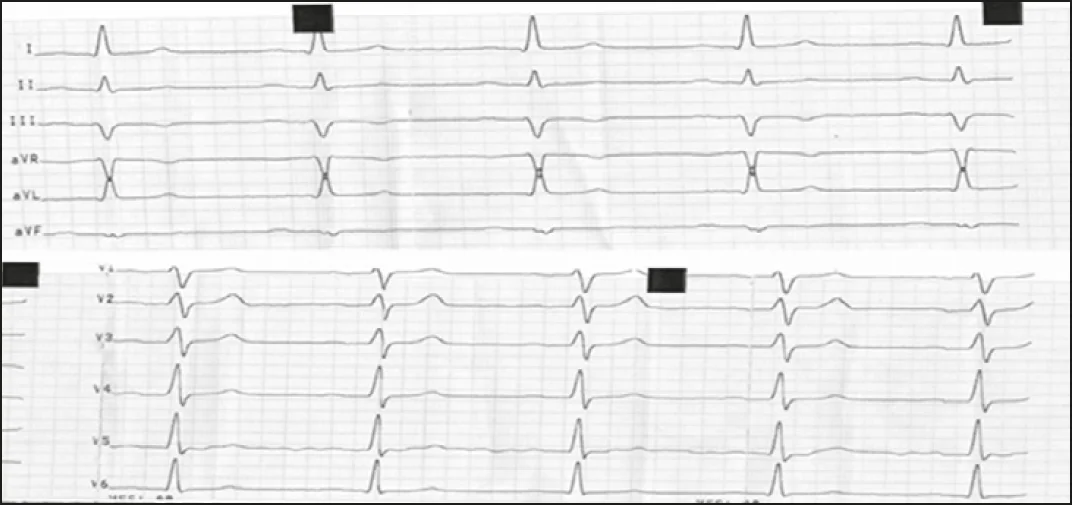

Обстеження. При первинному огляді пацієнтка стабільна. Має ожиріння I ст. (індекс маси тіла [ІМТ] – ​33,2 кг/м2). Офісний АТ – ​132/88 мм рт. ст., частота серцевих скорочень (ЧСС) – ​60 уд./хв, пульс неритмічний. На ЕКГ ритм синусовий, реєструється передсердна екстрасистолія за типом бігемінії (рис. 1). За даними ехокардіографії (ЕхоКГ), глобальна скоротливість лівого шлуночка (ЛШ) збережена (фракція викиду [ФВ] – ​56%), локальних порушень не зафіксовано. Товщина міжшлуночкової перегородки (МШП) – ​12 мм, задньої стінки ЛШ – ​11 мм. Діастолічна дисфункція ЛШ із нормальним тиском наповнення у спокої. Значної клапанної патології не визначається. У загальноклінічних та біохімічних аналізах відхилень немає. Тиреотропний гормон та рівень електролітів у нормі.

Рис. 1. ЕКГ пацієнтки  перед призначенням етацизинуРис. 1. ЕКГ пацієнтки перед призначенням етацизину